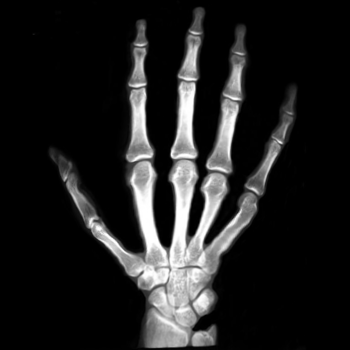

7.2. Real X-ray images

After testing our proposed method on several synthetic images, we now consider applying it on real medical images. Here, we consider a hand X-ray image as the source image (Fig. 7(a)) and a deformed hand X-ray image as the target image (Fig. 7(b)). Fig. 7(c) shows the original absolute intensity difference between the two images. It can be observed that different fingers are displaced in a nonuniform manner (for example, the displacement of the index finger is much larger than that of the little finger), while the wrist remains almost the same. Therefore, a simple rigid transformation is insufficient for yielding a good registration. As shown in Fig. 7(d), our proposed method successfully deforms the source image to match the target image, and the final intensity difference is significantly smaller (see Fig. 7(e)). From the deformed underlying grid in Fig. 7(f), it can be observed that the mapping is smooth and bijective. For comparison, both LDDMM [5] and DDemons [47] fail to register the fingers and are non-bijective (see Fig. 7(g), Fig. 7(h), and Fig. 7(i)).

We then consider another example of registering two hand X-ray images with larger deformations (see Fig. 8(a) for the source image, Fig. 8(b) for the target image, and Fig. 8(c) for their absolute intensity difference). The warped image produced by our proposed method (Fig. 8(d)) again closely resembles the target image with the intensity difference significantly reduced (see Fig. 8(e)). Fig. 8(f) shows that the mapping is smooth and bijective. For comparison, note that LDDMM [5] fails to match the fingers (Fig. 8(g)). While DROP [18] is capable of registering the fingers (Fig. 8(h)), it distorts the boundary shape of the overall image (Fig. 8(i)).